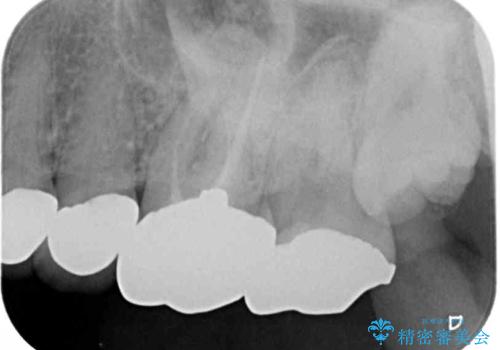

- 下顎の左右奥歯が痛みがあり、噛めないとのことで来院された患者様です。

左右ともに歯根が破折しており、抜歯が必要であったため、抜歯後にインプラント補綴治療を行うこととしました。

左側は骨欠損が著しいことが予想されるため、骨造成術並びに歯肉移植術を併用することとしました。